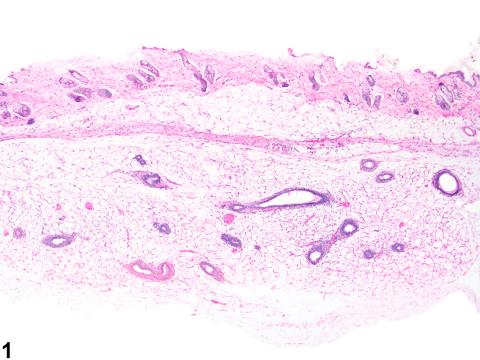

Mammary gland - Normal in a female B6C3F1/N mouse from an acute study. Normal mammary gland with well-developed mammary fat (adipose) pad and age appropriate ductular and acinar tissue.

Mammary gland - Normal in a female B6C3F1/N mouse from an acute study (higher magnification of Figure 1). Normal mammary gland with well-developed mammary fat (adipose) pad, ductules, and acini.